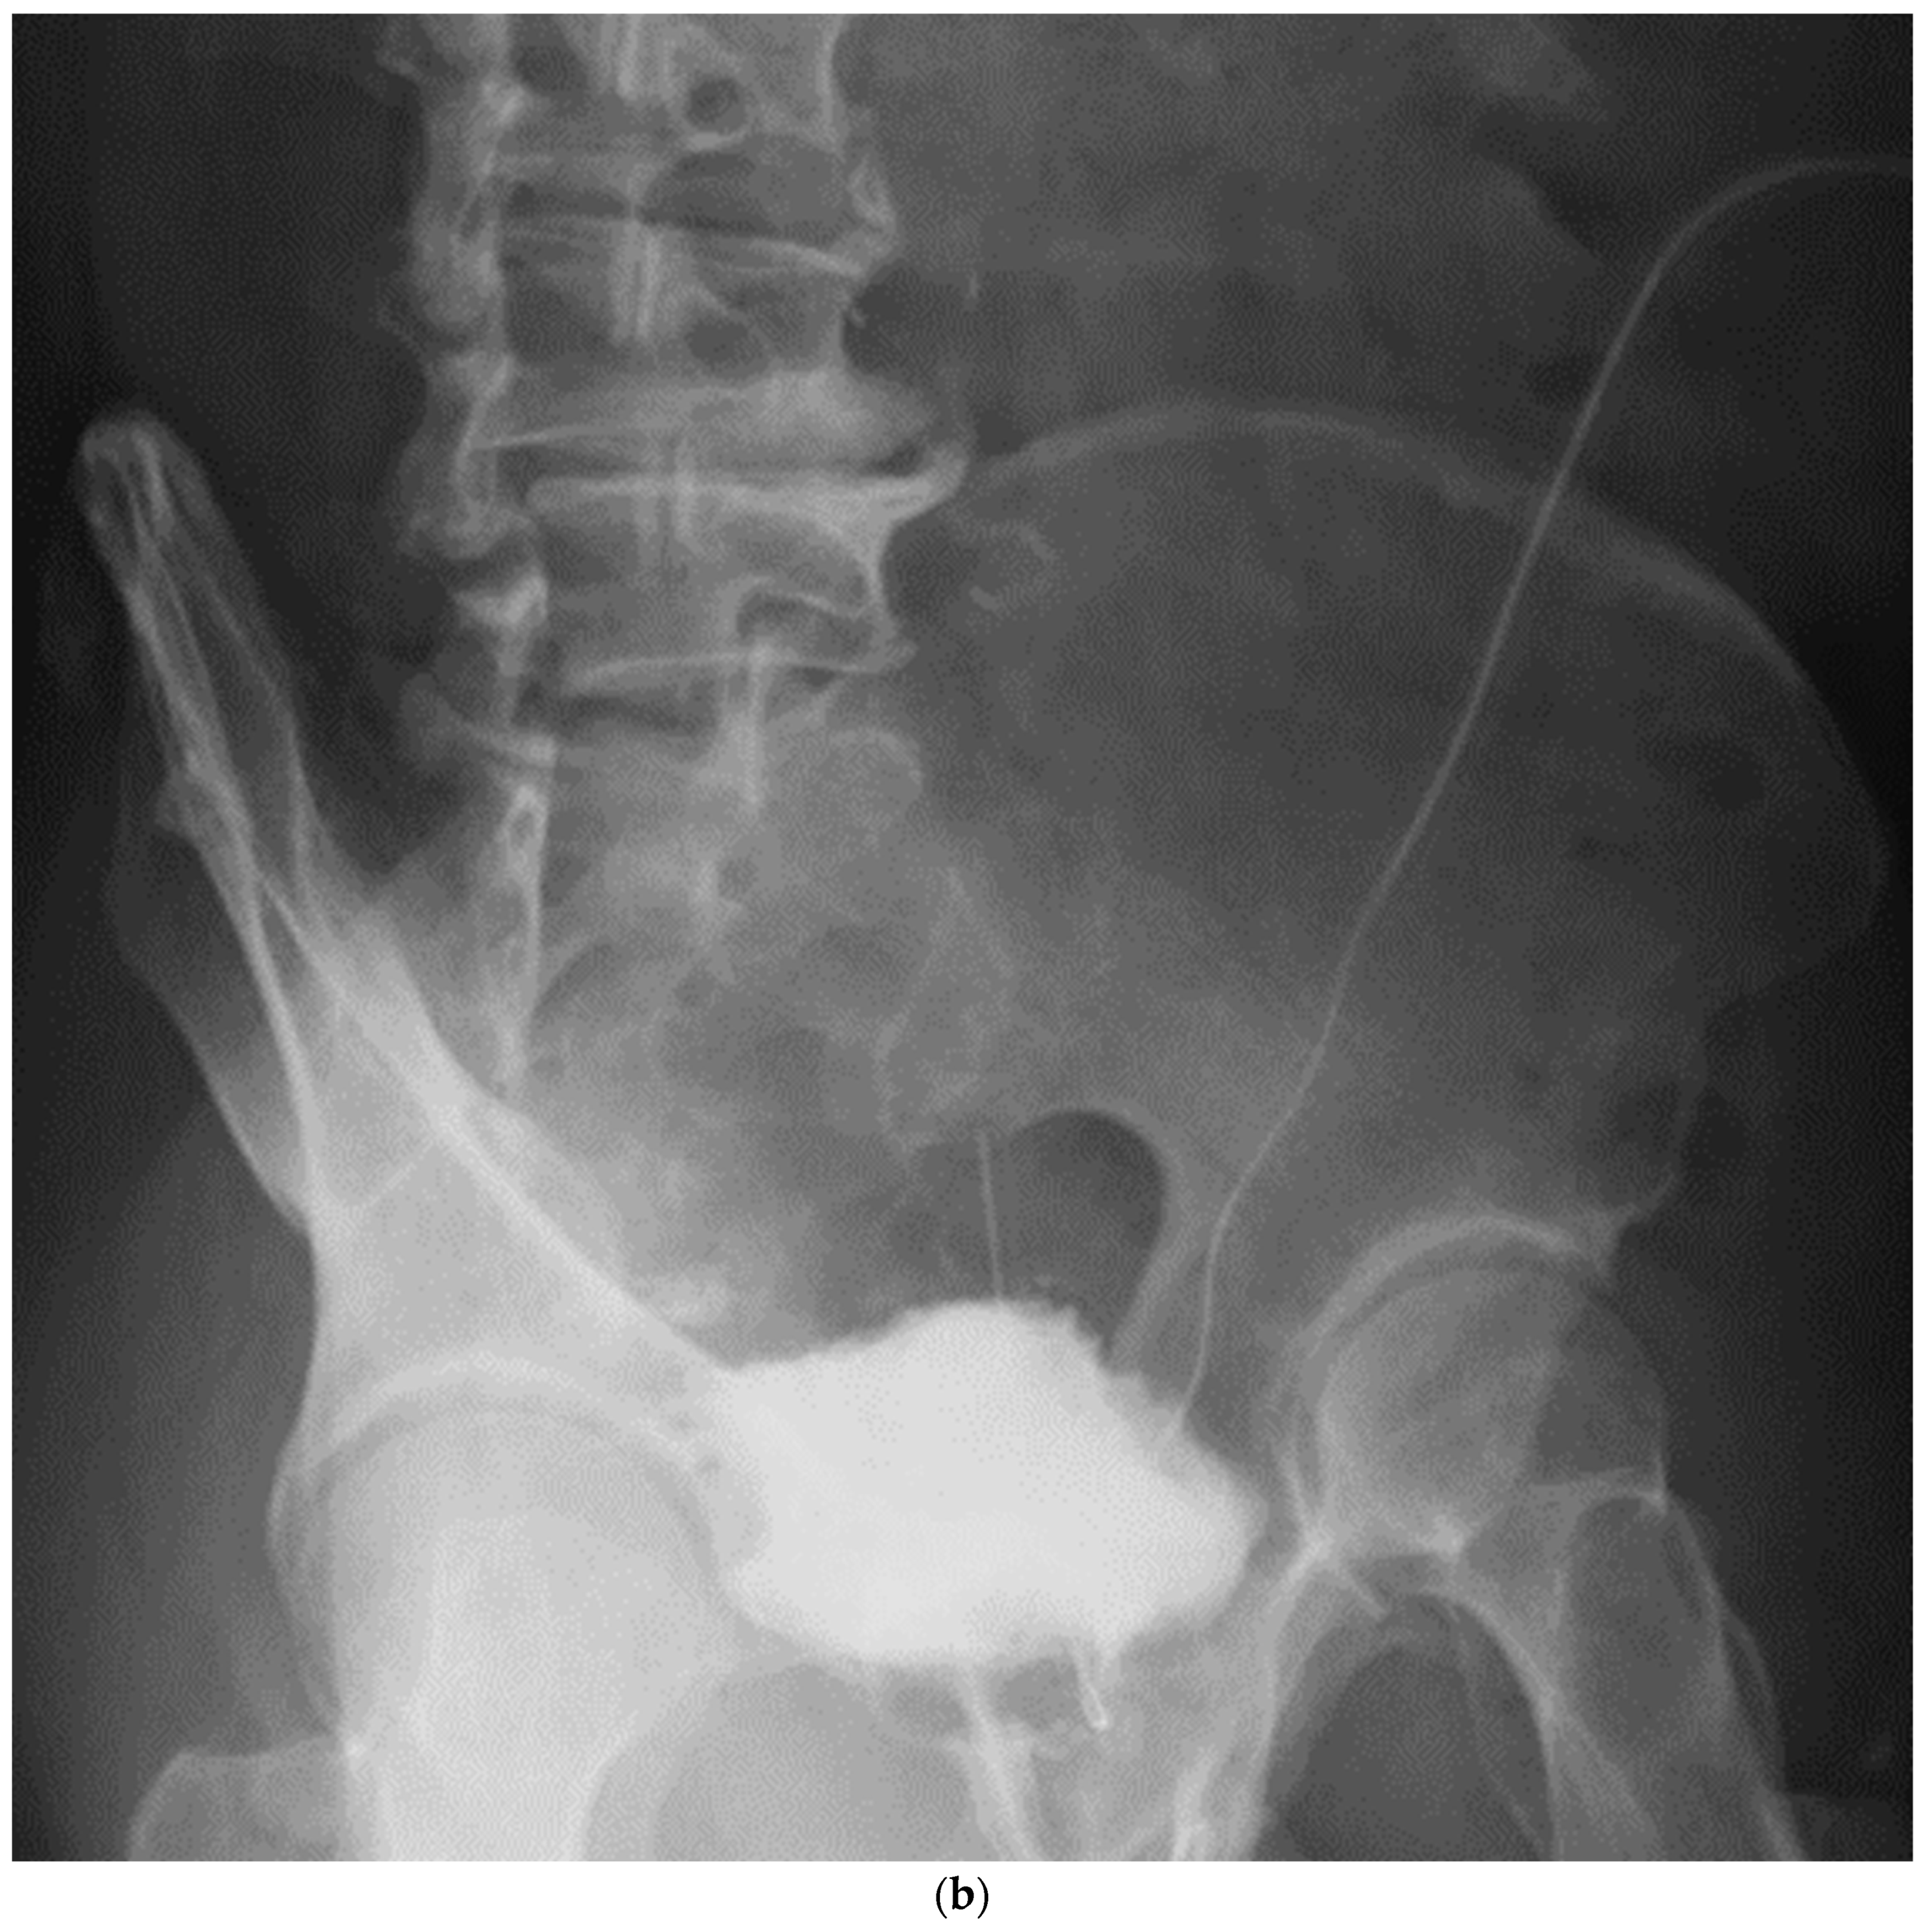

Figure 5.

Cystography at 2 weeks after surgery. (a). Frontal view, (b). Oblique view.

It maintained the spherical shape established using our technique.